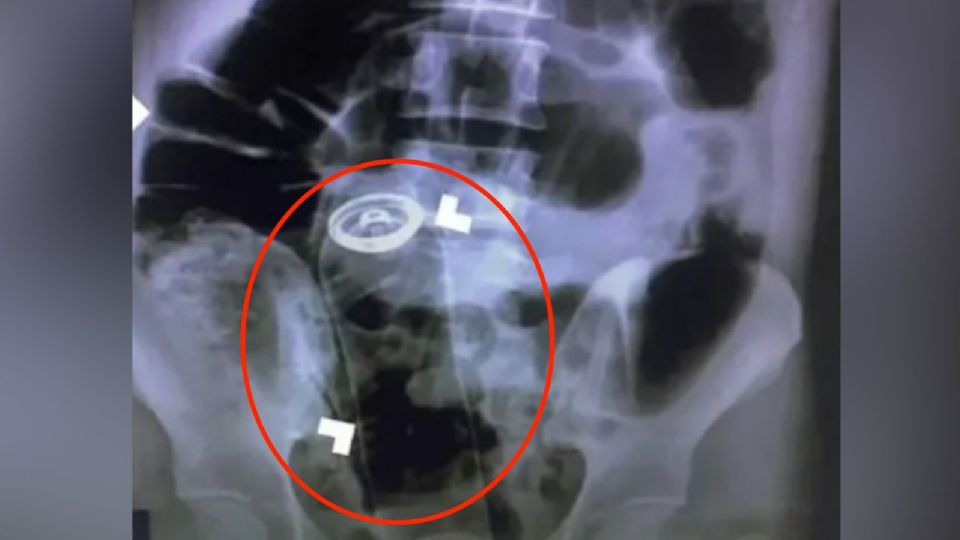

En la investigación se detalló que el paciente tenía demasiado dolor para una revisión rectal estándar, por lo que los médicos se vieron obligados a usar rayos X para descubrir que la botella de desodorante había viajado a su tracto digestivo. Tras el hallazgo, los cirujanos realizaron una incisión en el estómago del hombre y retiraron el antitranspirante.